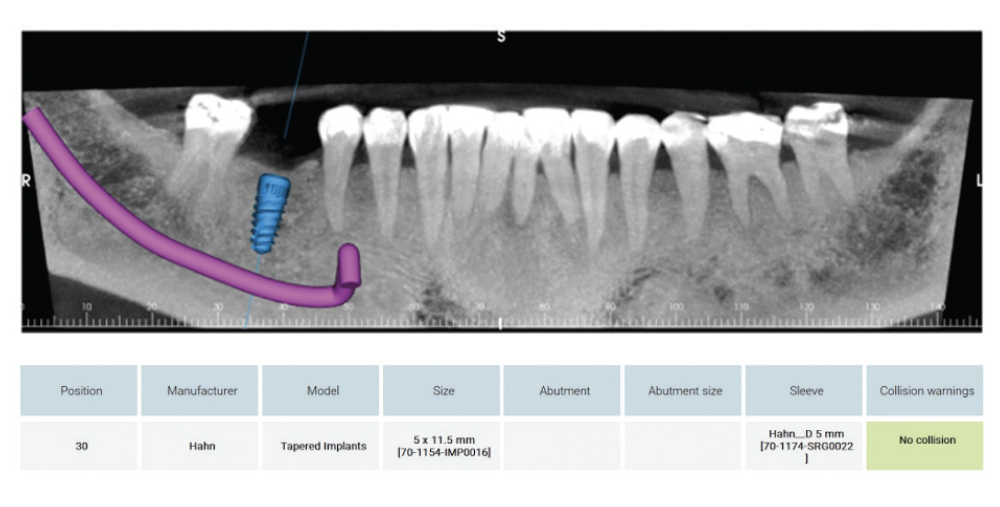

CBCT Scan and Schematics of Proposed Implant and Crown Placement

Figure 3: After a favorable intraoral assessment, a CBCT scan and preliminary reading were performed to confirm that the case was ready for the planning stage. The CBCT was then submitted to Glidewell’s Digital Treatment Planning (DTP) team, including a request that the team plan the case with a Glidewell HT™ Implant and the Glidewell HT Implant Guided Surgical Kit (Glidewell Direct; Irvine, Calif.). The report from DTP included a schematic of the proposed implant and crown placement, as well as the tooth-supported surgical guide. The placement of the crown was evaluated to ensure that it would be harmonious with the rest of the teeth in the arch and that it would provide the patient with proper function. I also ensured the implant followed the long axis of the proposed restoration, and that the screw access hole was in an acceptable esthetic position.

Mapping of the Interior Alveolar Nerve and the Metal Foramen

Figure 4: Mapping of the inferior alveolar nerve and the mental foramen (in purple) allowed an accurate evaluation of the implant placement, ensuring adequate distance from this structure.

Detailed Surgical Report Revealing Distance to Vital Structures

Figures 5a, 5b: An occlusal view clearly indicated the placement of the surgical guide and confirmed the trajectory the implant would follow as well as the position of the access hole on the occlusal surface. The detailed surgical report included a cross section revealing the implant’s proximity to vital structures. I could see the outline of the crown, the access channel, the outline of the implant (in blue), and the inferior alveolar nerve canal (in purple). I noted the distance between the implant and the nerve canal as well as the lingual concavity, another very important landmark when placing implants. To avoid complications, the plan maintained a safety zone of at least 2 mm.